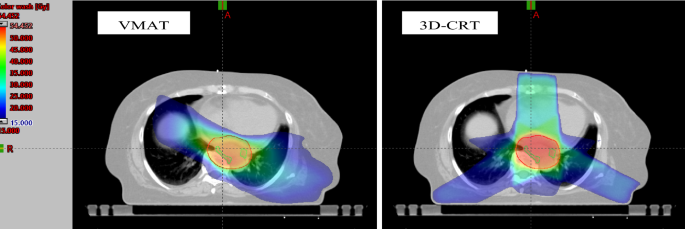

3D-CRT plans were generated with a median of 5 (range 4–8) coplanar beams, using 6 or 15 megaelectron volt (MV). Most of the monitor units (MUs) were delivered by left-posterior fields around 220°, right-posterior fields around 130° and an anterior field of 0° gantry rotation. For all VMAT plans, two complete arcs were used to deliver the planned dose, operating with photon energies of 6 MV or 15 MV. Regarding photon energies, 6-MV photons were used for 4 treatment plans (3D-CTRT) and 9 treatment plans (VMAT), while 15-MV photons were used for 19 treatment plans (3D-CRT) and 21 treatment plans (VMAT), respectively. Both 6-MV photons and 15-MV photons were used for 7 3D-CRT treatment plans. Thereby, the same photon energy was used for 3D-CRT and VMAT plans in 21 patients (70%). Figure 1 displays the dose distribution of 3D-CRT and VMAT plans using an exemplary patient.

Dose distribution of the VMAT (left) and the 3D-CRT (right) plans of an exemplary patient in transversal view. Circled in red: PTV; circled in green: lower thoracic paraesophageal lymph nodes (8L).

In general, compared to 3D-CRT, the usage of VMAT results in an improvement of target coverage and dose conformity, leading to a better sparing of normal tissue, which is shown by various studies12,13,14, including the previously mentioned study by Zhang et al.19. Our results confirm the superiority of VMAT regarding the sparing of OARs (see Fig. 1, see Table 2).

Nevertheless, differences between the two radiation techniques regarding Dmean and EUD did not reach significance in all of the 15 investigated nodal stations. Moreover, it should be noted that the absolute differences between the techniques were relatively small, only surpassing four Gray for the lymph nodes stations 7 and 15. This could at least partly be explained by the radial expansion from GTV to PTV, which leads to portions of the nodal stations being covered by the PTV. Therefore, the impact of the applied radiation technique on incidental nodal irradiation decreases for these stations (see Fig. 1), since the applied radiation technique only becomes relevant for portions of nodal stations outside of the PTV.